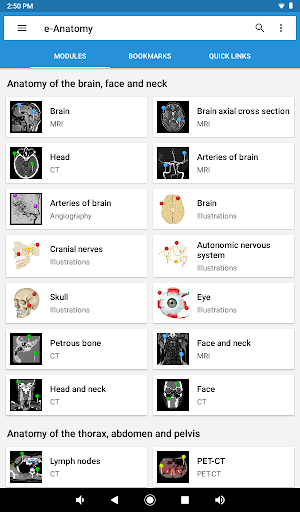

جديد: يمكنك الآن تصفية الوحدات حسب المنطقة أو نوع المحتوى حتى تتمكن من العثور على الوحدة التي تبحث عنها بشكل أسرع.

- وحدتان جديدتان: الدماغ - TOF والأوعية الدموية الدماغية ، أطلس التشريح الوعائي العصبي الطبيعي لشرايين الدماغ على الأوعية الدموية الدماغية. - تم إعادة صياغة الواجهة. - تتوفر علامة تبويب جديدة باسم "QuickLinks" ، ترسل وحدات في أقسام من جسم الإنسان وتسمح لك بالسفر السريع إلى الوحدات التي تبحث عنها. الخلل الصغيرة الثابتة.